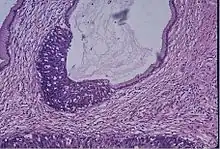

Cervical cancer

Cervical screening by the Pap test or other methods is highly effective at detecting and preventing cervical cancer, although there is a serious risk of overtreatment in young women up to the age of 20 or beyond, who are prone to have many abnormal cells which clear up naturally.[24] There is a considerable range in the recommended age at which to begin screening around the world. According to the 2010 European guidelines for cervical cancer screening, the age at which to commence screening ranges between 20–30 years of age, "but preferentially not before age 25 or 30 years", depending on the burden of the disease in the population and the available resources.[25]